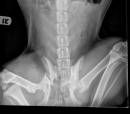

Colette has three Tick-Borne Diseases that are significant. If we do not get them under control, she will die based on how sick she has been.  She has tested positive for multiple tick-borne diseases including Bartonella, Rickettsia, and Ehrlichia.  Based on her antibody levels, Dr. Welch suspects that her Bartonella and Rickettsia are the primary causes of her chronic intermittent fever and recurrent joint effusion (accumulation of fluid) and pain.

Each Disease requires a different antibiotic for an extended period. We have just started our third antibiotic for this beautiful pup.   When her joints swell with fluid, her fever returns, and she has to go back to ICU and have her joints tapped. The more times we tap the joints, her chances go up for getting an infection in the joint.   If we can get her fever down by not tapping the joints, we have made progress.  The problem is that even on IV fluids, we have had a hard time getting her fever down.

When Colette's joints fill, she has terrible pain and no longer wants to walk. She will get up, take a few steps and then lay down.  She feels awful because her legs hurt and her body aches from the fever. It breaks our hearts for this amazing dog.  She will have a few good days when she returns, and then the cycle begins again.